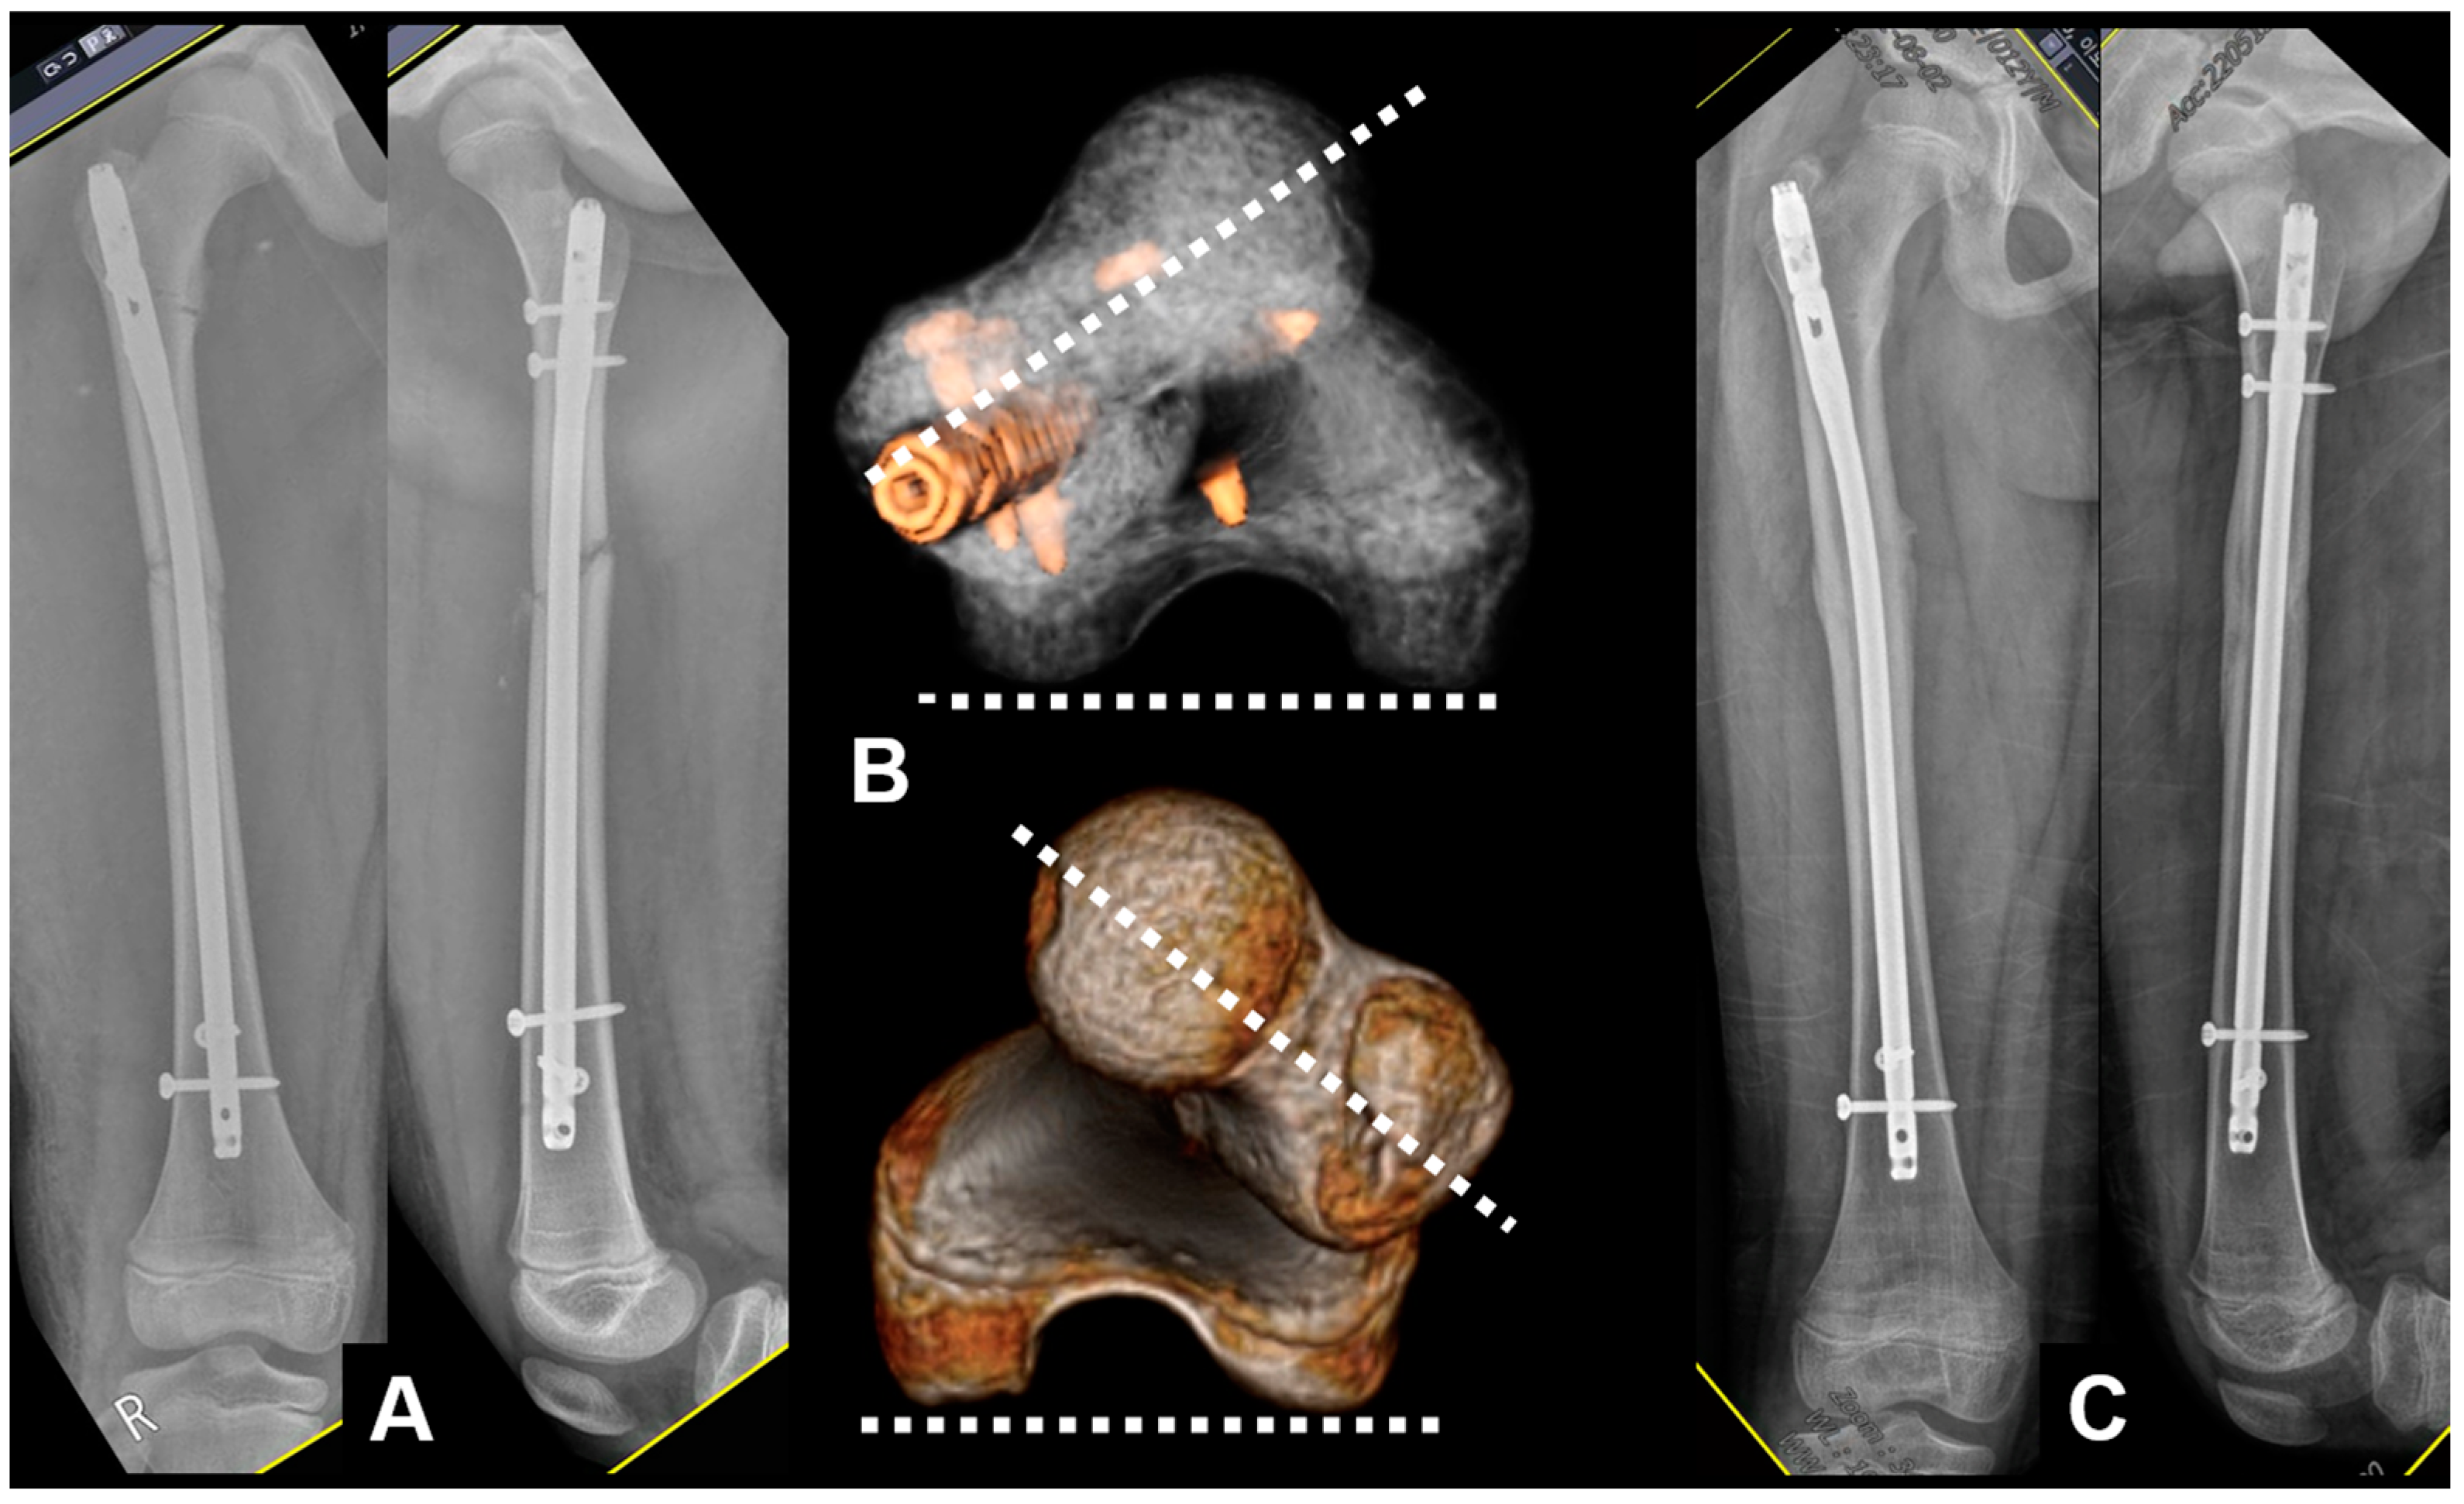

2.1. Surgical Technique

2.2. Smart Phone Application

| No. | Sex | Age (Year) | Location | Cause | Rotational Deformity | Associated Deformity | Implant | Bone Graft | Pre- Operative Difference | Angle Measured Using SP App | Post- Operative Difference | Gained Angle | Time to Union (Weeks) |

|---|---|---|---|---|---|---|---|---|---|---|---|---|---|

| 1 | M | 15 | Femur | Malalignment | Internal | Nail | none | 16.1 | 15.8 | 2.3 | 13.8 | 12 | |

| 2 | M | 37 | Femur | Nonunion | External | Nail | YES | 38.3 | 36.1 | 3.2 | 35.1 | 16 | |

| 3 | M | 22 | Femur | Malalignment | External | Nail | none | 22.3 | 20.9 | −1.5 | 23.8 | 16 | |

| 4 | M | 49 | Femur | Malunion | External | Varus | Nail | YES | 15.6 | 14.1 | 1.4 | 14.2 | nonunion |

| 5 | F | 32 | Femur | Nonunion | Internal | Nail | YES | 27.8 | 29.5 | 4.3 | 23.5 | 18 | |

| 6 | M | 50 | Femur | Malunion | Internal | Varus | Plate | none | 20.2 | 20.3 | −2.1 | 22.3 | 16 |

| 7 | M | 57 | Femur | Nonunion | External | Nail | none | 20 | 19.2 | −4.2 | 24.2 | 18 | |

| 8 | M | 70 | Femur | Nonunion | External | Nail | YES | 35.9 | 35.3 | −3.3 | 39.2 | 20 | |

| 9 | M | 57 | Femur | Nonunion | Internal | Nail | YES | 23.5 | 22.2 | 2.5 | 21 | 24 | |

| 10 | M | 58 | Femur | Nonunion | External | Nail | YES | 11.2 | 10.4 | −2.7 | 13.9 | 20 | |

| 11 | M | 46 | Femur | Nonunion | External | Nail | YES | 23.9 | 23.4 | 4.8 | 19.1 | 18 | |

| 12 | M | 11 | Femur | Malalignment | External | Nail | none | 20.6 | 20.1 | −1.6 | 22.2 | 14 | |

| 13 | M | 27 | Femur | Nonunion | Internal | Nail | none | 21.8 | 20.5 | 4.2 | 17.6 | 18 | |

| 14 | M | 24 | Femur | Malunion | Internal | Varus | Nail | none | 17.8 | 19.6 | 3.0 | 14.8 | 16 |

| 15 | F | 15 | Tibia | Malalignment | Internal | Procurvatum | Plate | none | 16.3 | 14.7 | 1.3 | 15 | 14 |

| 16 | M | 77 | Femur | Nonunion | External | Nail | none | 23.1 | 20.2 | 4.6 | 18.5 | 20 | |

| 17 | M | 17 | Femur | Nonunion | External | Nail | YES | 17.2 | 15.9 | 2.5 | 14.7 | 20 | |

| 18 | M | 20 | Tibia | Malunion | External | Nail | none | 30.3 | 32.5 | 1.5 | 28.8 | 20 | |

| 19 | M | 36 | Femur | Nonunion | Internal | Nail | none | 22.1 | 19.3 | −1.8 | 23.9 | 18 | |

| 37.9 | 22.3 | 21.6 | 2.3 | 21.3 | 17.7 |